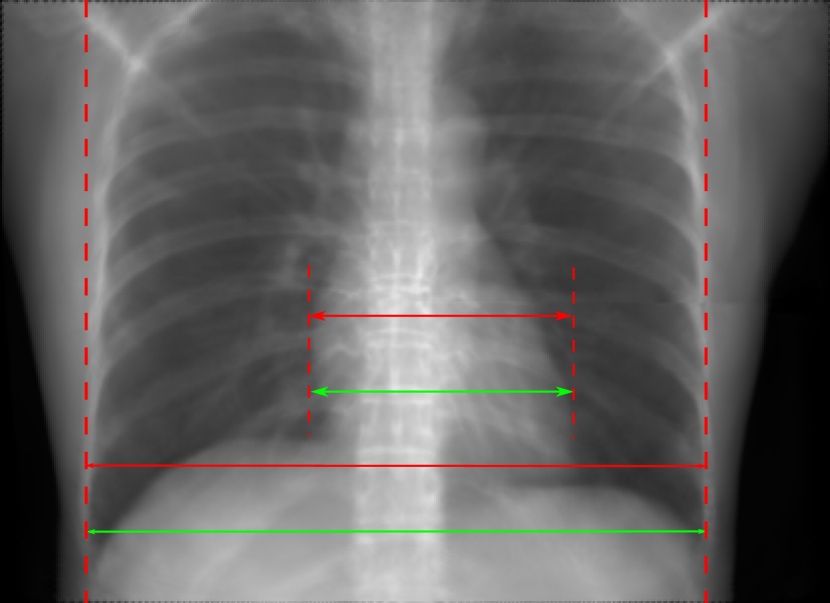

5.1 Chest Data

Refer to caption

(a) Reference

(b) 0superscript00^{\circ} perspective

(c) (b)-(a)

0.4237, -, -

0.4002, 17.01, 0.6532

Pix2pixGAN

(d) 0superscript00^{\circ} Cartesian

(e) 0&180superscript0superscript1800^{\circ}\&180^{\circ} Cartesian

(f) 0&180superscript0superscript1800^{\circ}\&180^{\circ} polar

0.4303, 7.08, 0.8535

0.4214, 5.37, 0.9098

0.4240, 3.83, 0.9536

(g) (d)-(a)

(h) (e)-(a)

(i) (f)-(a)

TransU-Net

(j) 0superscript00^{\circ} Cartesian

(k) 0&180superscript0superscript1800^{\circ}\&180^{\circ} Cartesian

(l) 0&180superscript0superscript1800^{\circ}\&180^{\circ} polar

0.4272, 10.92, 0.8222

0.4281, 9.37, 0.8424

0.4248, 8.12, 0.8859

(m) (j)-(a)

(n) (k)-(a)

(o) (l)-(a)

Figure 10: Perspective deformation learning in one exemplary patient case for chest X-ray imaging. The maximal horizontal cardiac diameter and the maximal horizontal thoracic diameter in (b) and (d)-(f) are indicated by the horizontal red lines, while those in the reference image (a) are green lines. The cardiothoracic ratio, RMSE, and SSIM for each image is displayed in its corresponding subcaption.

The results of one patient in chest X-ray imaging are displayed in Fig. 10, where the cardiothoracic ratio is assessed as an exemplary clinical application [32]. In the reference image (Fig. 10(a)), the maximal horizontal cardiac diameter (MHCD) and the maximal horizontal thoracic diameter (MHTD) are indicated by two green horizontal lines. Its cardiothoracic ratio is 0.4237. In the 0superscript00^{\circ} perspective projection image (Fig. 10(b)), all the anatomical structures can be visualized with fine resolution. However, due to perspective deformation, anatomical structures, e.g. the ribs and the spine, are deformed. The deformations are visualized better in the difference image Fig. 10(c). Compared with the ribs and the spine, the heart has less deformation as its location is closer to the isocenter. In Fig. 10(b), the MHCD and the MHTD are indicated by two red horizontal lines, while the green lines are those of the reference image. While the MHCD has changed little from 10.47 cm to 10.16 cm, the MHTD has changed considerably from 24.71 cm to 25.40 cm. As a consequence, the cardiothoracic ratio becomes 0.4002, which is below the normal range of 0.42 - 0.50 [32]. The result of learning perspective deformation from 0superscript00^{\circ} single view is displayed in Fig. 10(d), where the MHCD and the MHTD are 10.63 cm and 24.71 cm, respectively. The MHTD of Fig. 10(d) is the same as that of the reference image. This is also reflected by the difference image Fig. 10(g), where the lower ribs have small errors. However, the upper ribs as well as the spine still have considerable errors. The results of perspective deformation learning from 0&180superscript0superscript1800^{\circ}\&180^{\circ} views in Cartesian and polar coordinates are displayed in Fig. 10(e) and Fig. 10(f), respectively. The measured MHCDs and MHTDs in these two images are very close to the reference ones. Hence, their cardiothoracic ratios, 0.4214 and 0.4240 respectively, are close to the reference ratio as well. In the difference images (Fig. 10(h) and Fig. 10(i)), the errors of ribs and spine decrease as their boundaries are no longer apparently visible. Nevertheless, Fig. 10(i) has less error than Fig. 10(h), achieving the smallest RMSE value of 3.83. The quantitative evaluation of all the 162 testing datasets is displayed in Tab. II, where learning perspective deformation from two complementary views in polar coordinates achieves the least RMSE 4.98 and highest SSIM 0.9517, demonstrating the superiority of learning perspective deformation from two complementary views in polar coordinates.

The TransU-Net results are displayed in Figs. 10(j)-(l). Compared with their corresponding Pix2pixGAN results, the TransU-Net prediction images are more blurry, although the same perceptual loss is used. The error images in Figs. 10(m)-(o) indicate that TransU-Net reduces perspective deformation better with complementary views than a single view. The quantitative evaluation in Tab. II shows that TransU-Net cannot effectively reduce perspective deformation with a single view. With complementary views in both Cartesian and polar coordinate systems, TransU-Net achieves comparable performance, which is still considerably worse than that of Pix2pixGAN. The inferior performance of TransU-Net to Pix2pixGAN on the chest data is potentially caused by the repetitive nature of the segmental rib anatomy, which leads TransU-Net to be ineffective in extracting position-dependent features.